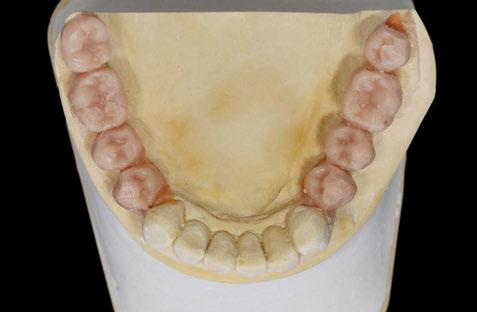

Figuras 11 y 12. Modelos realizados por CAD/CAM con los encerados de los dientes a reponer en los sectores posteriores mandibulares, montados en el articulador para generar una oclusión óptima.

Figuras 13-15. Imágenes del cone-beam de planificación de los cortes mandibulares de los tres implantes de 4,5 mm de longitud. Como podemos observar en los tres casos, la atrofia en altura es muy llamativa, habiéndose necesitado procedimientos regenerativos previos en caso de haber colocado implantes de longitud convencional.